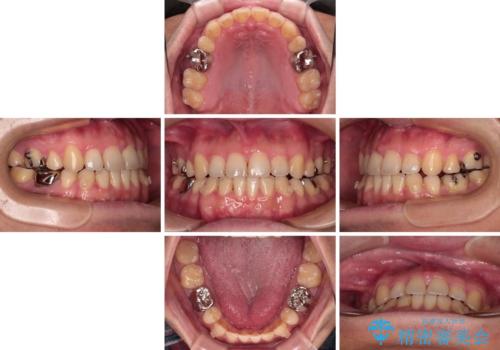

- 抜歯矯正の後戻りを気にして来院された患者様です。

舌の突出癖によるオープンバイトになり、前歯の叢生が後戻りしていました。

舌のトレーニングを行いながら、インビザラインを用いて矯正治療を行うこととしました。

インビザラインの特性を活用して奥歯の咬み合わせを圧下させることで、前歯のオープンバイトを改善さえることができました。